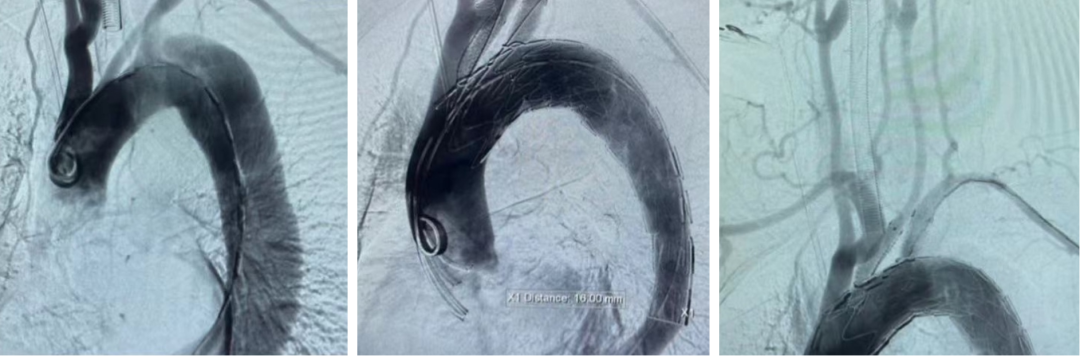

病例二(双开窗)

汪XX,男,52岁,主动脉夹层。LSA、LCCA双开窗。

术中